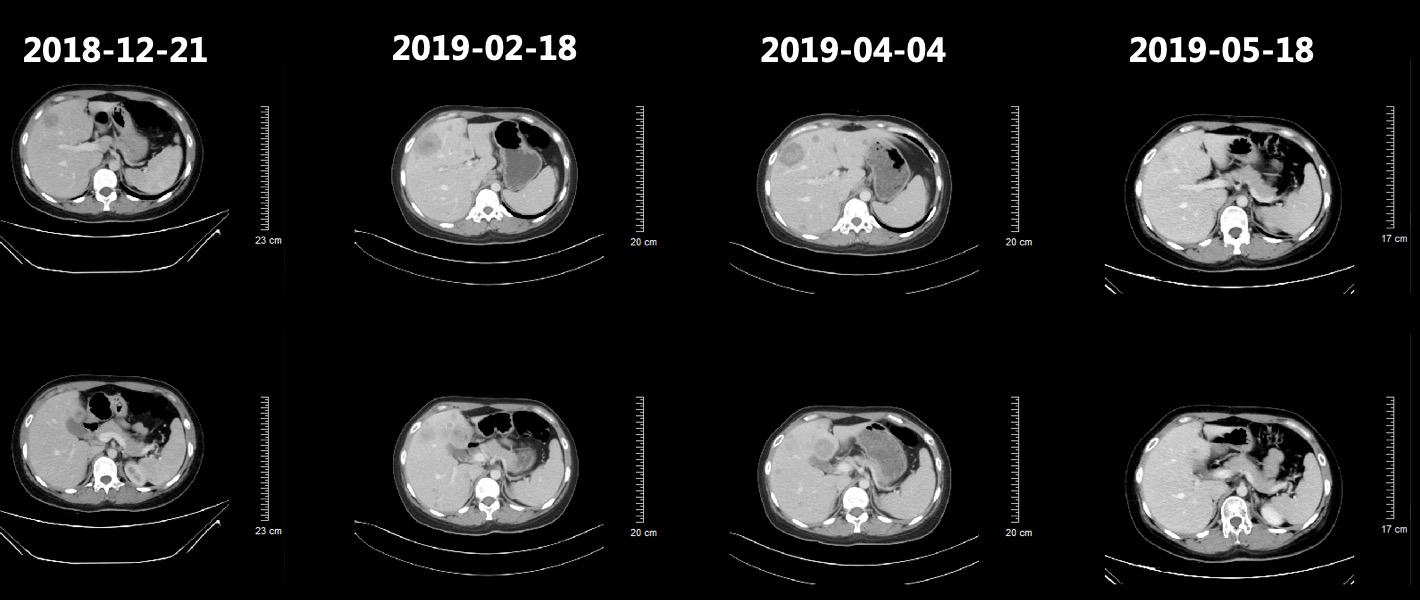

患者于2018-12-26、2019-01-19分别行第1-2周期TC方案(紫杉醇脂质体+卡铂,每3周1次),患者基线和化疗后肿瘤标志物变化如图3所示,肺和肝脏病灶变化影像如图4所示,2019-02-18复查CT提示肺部病灶稳定(缩小),肝脏病灶增多增大,总体疗效评价疾病进展(PD)。

图4 患者基线和化疗后肺部病灶和肝脏病灶对比影像,肺部病灶缩小,肝脏病灶增多增大